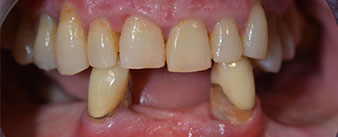

The 64-year-old patient presented with residual dentition of teeth 38, 33 and 43 and a clasp denture in the mandible (Fig. 1 and 2).

Fig. 1

Fig. 2